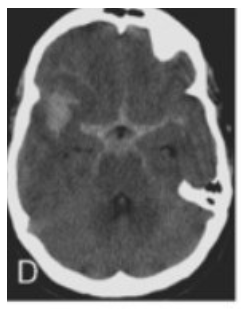

An urgent cerebral CT angiogram has been performed and an image from the CT is displayed.

The neurosurgical team wishes to urgently perform a craniotomy and clip a presumed ruptured right middle cerebral artery aneurysm.

image.png

What is your approach to assessing and managing the patient prior to surgery?